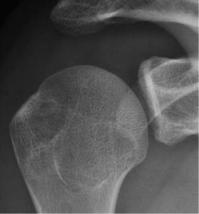

对于关节盂及肱骨的骨缺损是通过正位X线检查来评估的。

对肱骨骨缺损的评估:

需要在肩关节内旋位、中立位、外旋位时分别拍摄3张正位X线,来评估有无Hill-Sachs损伤。

通过正位X线看关节盂下方是否存在撕脱性骨折或者是轮廓的丢失。

正常

关节盂下缘撕脱性骨折

关节盂下缘轮廓丢失

如在肩关节外旋位的正位X线上能看到Hill-Sachs损伤,则评分应为2分;

如果正位X线上能看到关节盂下缘的轮廓丢失,则同样应为2分。